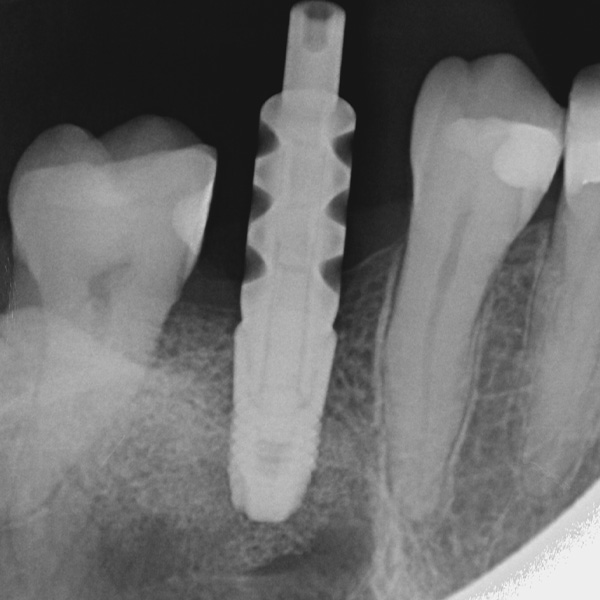

Sobre todo las restauraciones sobre implantes están sometidas a elevadas solicitaciones. Tras la extracción y el implante, al paciente le falta el tejido fibroso elástico del lecho dental natural. En consecuencia, no se absorben las fuerzas oclusales, sino que se transmiten directamente a la restauración, al implante, al hueso y a los dientes antagonistas. La cerámica híbrida VITA ENAMIC incorpora una matriz dual de cerámica (86 % del peso) y polímero (14 % del peso). Esto le otorga una elasticidad similar a la de la dentina y la capacidad de absorber fuerzas oclusales. Gracias a su elevada dimensión vertical, la pieza en bruto policroma VITA ENAMIC multiColor en la geometría EMC-16 posibilita, incluso en caso de hueso atrofiado, la confección de coronas sobre pilar monolíticas de una pieza. El doctor y catedrático Alexander Hassel muestra en el siguiente artículo cómo ha tratado a una paciente empleando este método de restauración.